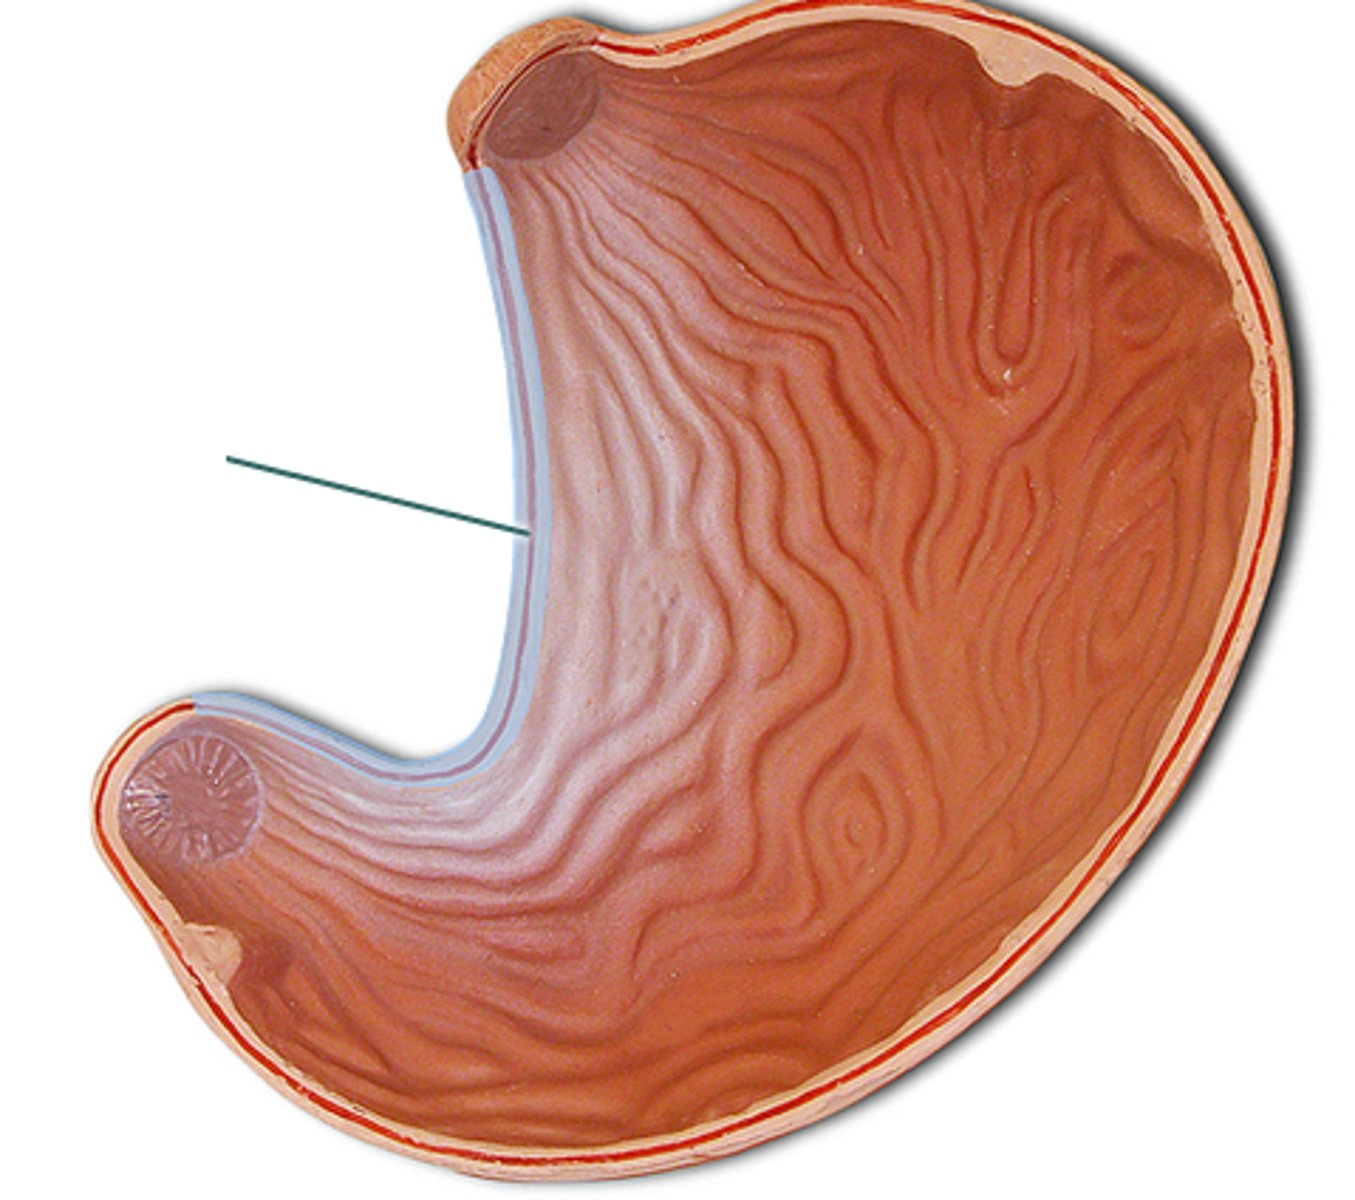

stomach

fundus

cardia

body

lesser curvature

greater curvature

cardiac sphincter / lower esophageal sphincter

pylorus

pyloric sphincter

rugae